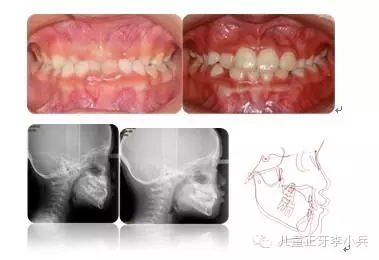

1. 兒童牙病的治療與錯(cuò)合畸形的預(yù)防:兒童齲病造成牙冠橫徑變短、乳牙早失、磨牙前移。兒童根尖周病影響恒牙發(fā)育及萌出異常,阻生。兒童牙病治療、間隙維持能預(yù)防繼承恒牙的萌出異常。(圖2,病例一)

圖2 75深齲,34牙胚萌出異常,拔出75,舌弓間隙維持后,34萌出道自行調(diào)整萌出;